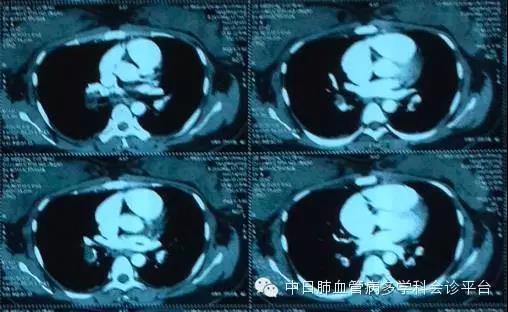

(2015-12-05,CTPA,纵隔窗)

(2015-12-05,CTPA,肺窗)